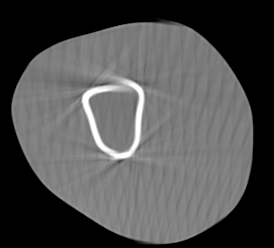

Involuntary subject motion is the main source of artifacts in weight-bearing cone-beam CT of the knee. To achieve image quality for clinical diagnosis, the motion needs to be compensated. We propose to use inertial measurement units (IMUs) attached to the leg for motion estimation. We perform a simulation study using real motion recorded with an optical tracking system. Three IMU-based correction approaches are evaluated, namely rigid motion correction, non-rigid 2D projection deformation and non-rigid 3D dynamic reconstruction. We present an initialization process based on the system geometry. With an IMU noise simulation, we investigate the applicability of the proposed methods in real applications. All proposed IMU-based approaches correct motion at least as good as a state-of-the-art marker-based approach. The structural similarity index and the root mean squared error between motion-free and motion corrected volumes are improved by 24-35% and 78-85%, respectively, compared with the uncorrected case. The noise analysis shows that the noise levels of commercially available IMUs need to be improved by a factor of $10^5$ which is currently only achieved by specialized hardware not robust enough for the application. The presented study confirms the feasibility of this novel approach and defines improvements necessary for a real application.